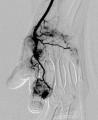

[画像5:

https://prcdn.freetls.fastly.net/release_image/52582/16/52582-16-fd6abb75f4116e4d3315c5de29b7f1a1-233x285.png?width=536&quality=85%2C75&format=jpeg&auto=webp&fit=bounds&bg-color=fff ]

手にできた不要な血管「モヤモヤ血管」